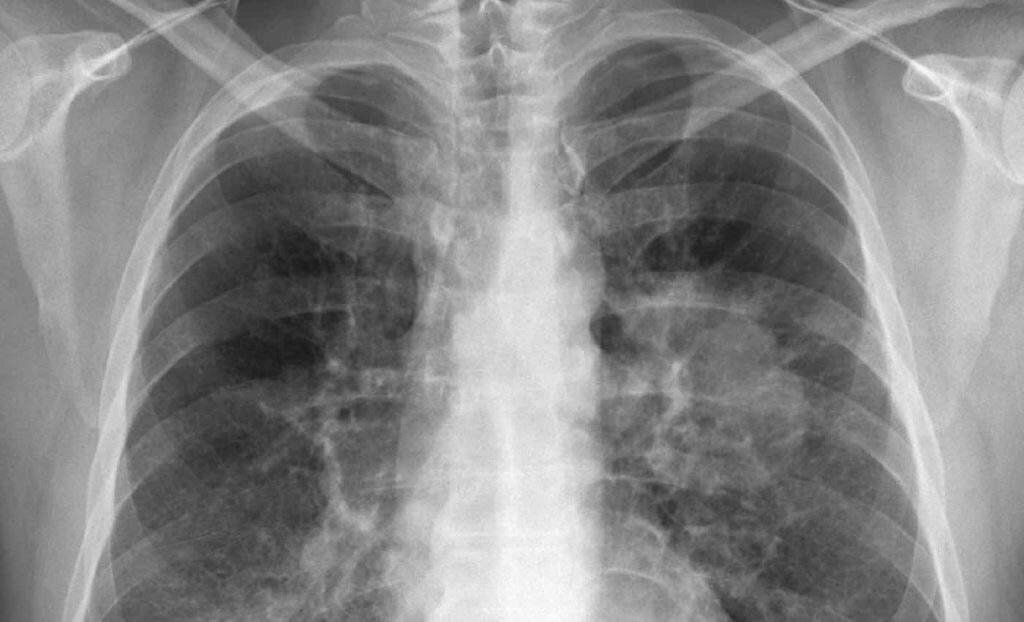

Radiografía de un cáncer de pulmón